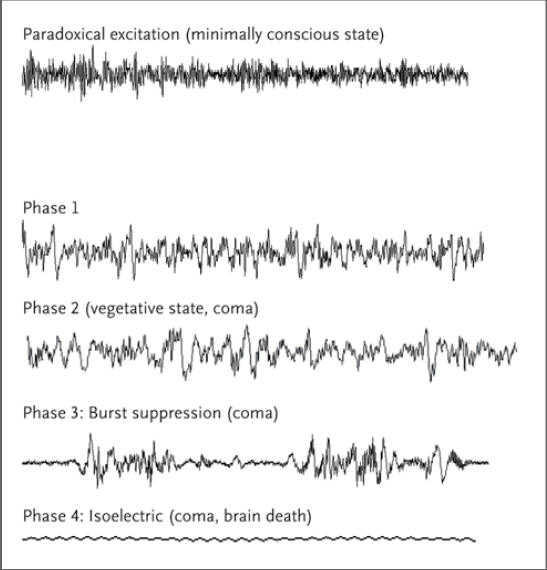

哈佛大学医学院的一个特别委员会建议修改死亡的定义,这促使遭受毁灭性神经损伤的病人可能成为器官移植的供体。这个脑死亡的概念成为了无数的器官捐献和移植在法律上和伦理上的依据。